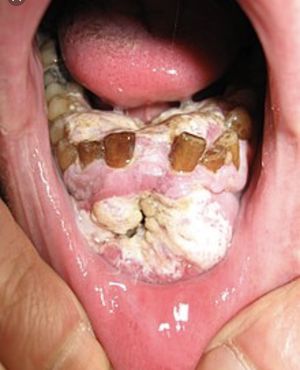

Historically the death rate associated with this cancer is particularly high not because it is hard to discover or diagnose, but due to the cancer being routinely discovered late in its development.Often oral cancer is only discovered when the cancer has metastasized to another location, most likely the lymph nodes of the neck. Prognosis at this stage of discovery is significantly worse than when it is caught in a localized intra oral area. Besides the metastasis, at these later stages, the primary tumor has had time to invade deep into local structures.Oral cancer is particularly dangerous because in its early stages it may not be noticed by the patient, as it can frequently prosper without producing pain or symptoms they might readily recognize, and because it has a high risk of producing second, primary tumors. This means that patients who survive a first encounter with the disease, have up to a 20 times higher risk of developing a second cancer. This heightened risk factor can last for 5 to 10 years after the first occurrence. There are several types of oral cancers, but around 90% are squamous cell carcinomas. It is estimated that approximately $3.2 billion is spent in the United States each year on treatment of head and neck cancers. (2010 numbers)